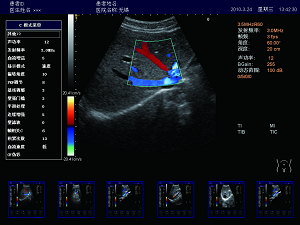

實時三同步

B型、彩色和頻譜多普勒三種模式同時實時顯示,獲

得更精確地采樣定位,更直觀進行對比分析。

實時顯微成像、一鍵優(yōu)化

肝臟 脾臟 多普勒血流